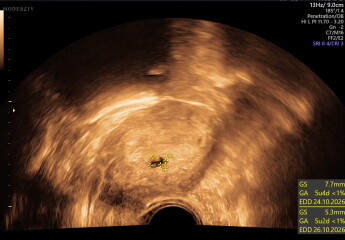

scan at 5 weeks 3 days, no heartbeats but possible twins (picture)

she then said the weird thing was that she thought she could see two sacs. she said she thought she saw it on the external scan & then on the internal when she checked. but she said it was hard to recreate the images again & then one was too blurry to see anything. from what she could measure on one it measured as 5 week2 days so pretty in line with what i thought. I have never even considered multiples, zero history in my family & I am not so old so i was shocked. she seemed very unsure but again dont know how careful she was being then said i would have to come in a weeks time, & if i needed anything in the meantime let her know

Ive attatched pictures if anyone is any good at reading, i dont feel ready to talk to anyone in real life about this yet